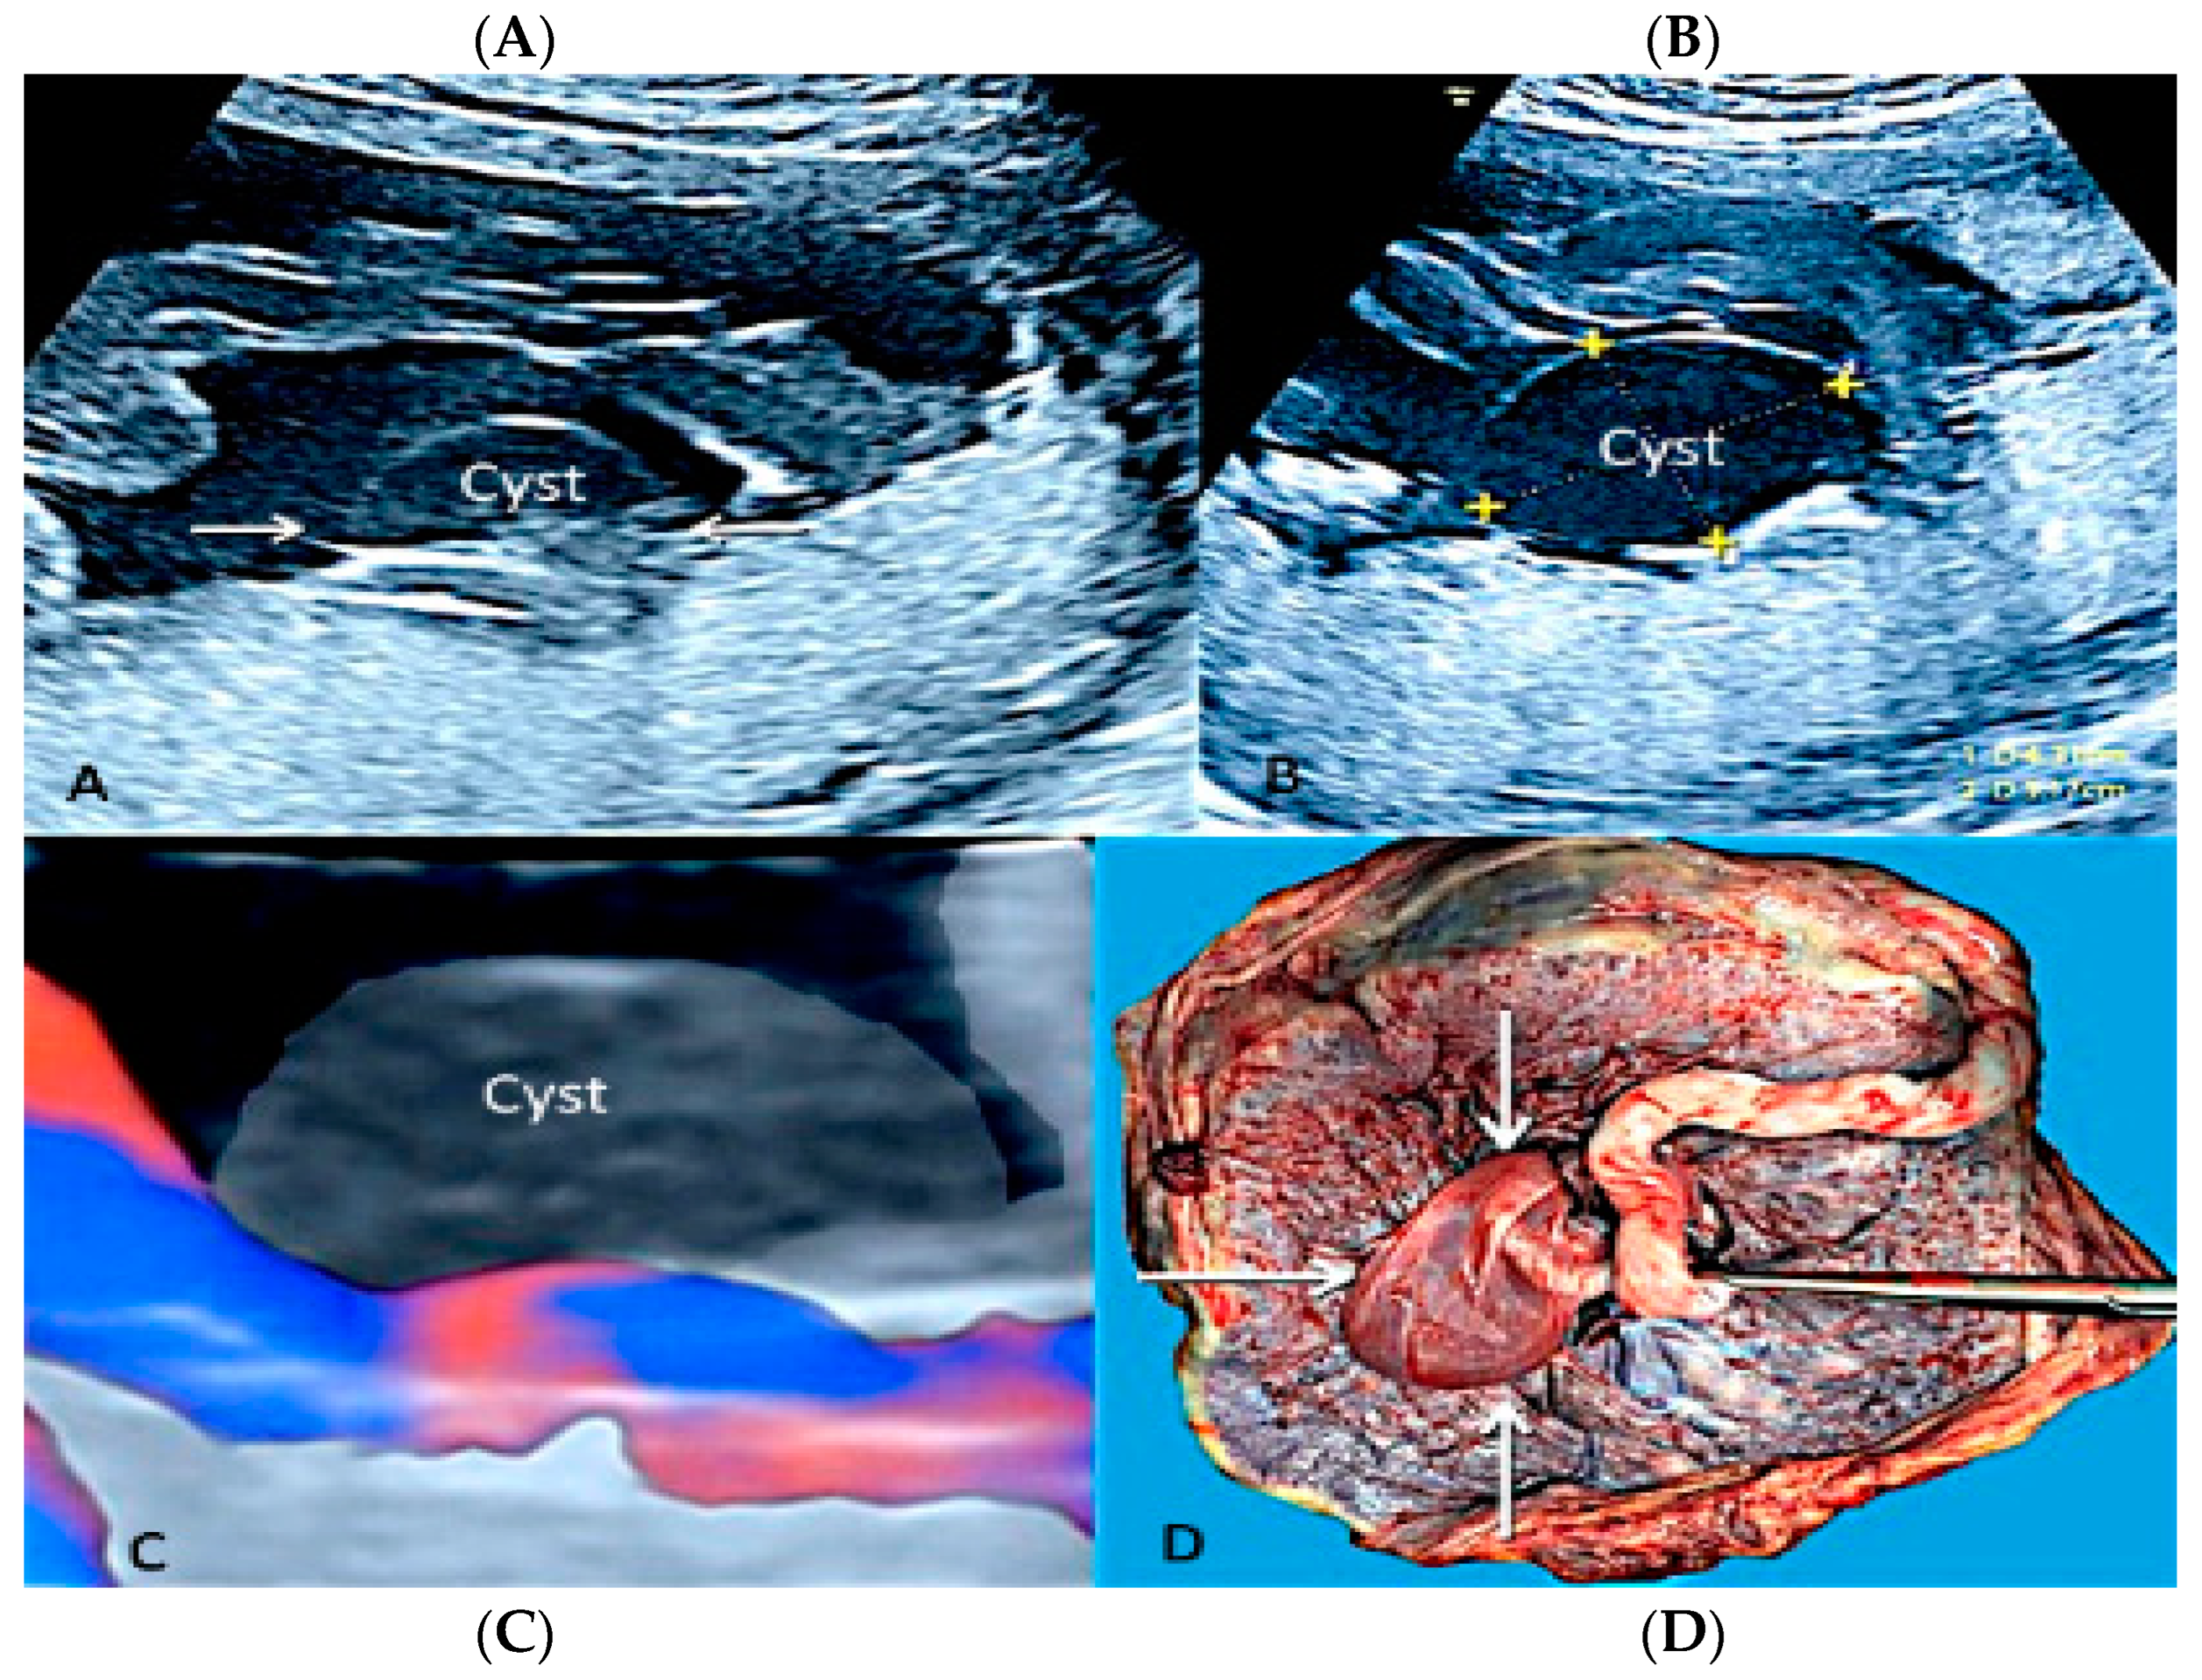

3.1.7. Membranous Placental Cysts

- Brown, D.L.; DiSlavo, D.N.; Frates, M.C.; Davidson, K.M.; Genest, D.R. Placental surface cysts detected on sonography: Histiologic and clinical correlation. J. Ultrasound Med. 2002, 1, 641–646. [Google Scholar]